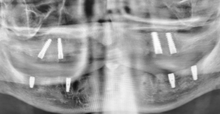

ВАЖНО! В нашей клинике человеческий фактор полностью нивелируется посредством навигационной хирургии и использованием цифрового протокола лечения. Этот протокол предусматривает сбор и анализ рентгеновских снимков и моделей полости рта пациента с переводом этих данных в цифровой вид. Это позволяет планировать реализацию постановки импланта и вид будущей коронки еще до этапа имплантации.